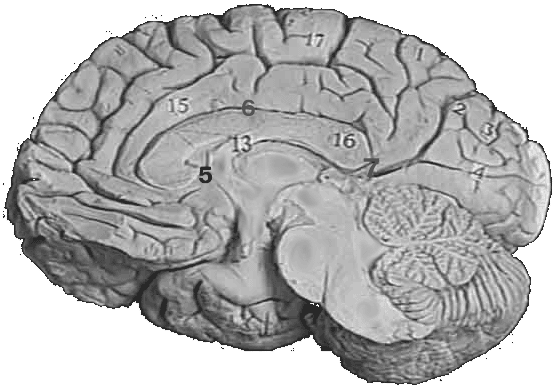

Рис. 3. Медиальная поверхность головного мозга.

1-Precuneus

2-Sulcus parietooccipitalis

3-Cuneus

4-Fissura calcarina

5-Uncus

6-Sulcus corporis collosi

13-Fornix

15-Gyrus cinguli

16-Splenium corporis collosi

17-Lobulus paracentralis

На медиальной поверхности полушария находится борозда мозолистого тела (sulcus corporis callosi), идущая непосредственно над мозолистым телом и продолжающаяся своим задним концом в глубокую sulcus hippocampi, которая направляется вперед и книзу. Параллельно и выше этой борозды проходит по медиальной поверхности полушария sulcus cinguli. Парацентральной долькой (lobulus paracentralis) называется небольшой участок над язычковой бороздой. Кзади от парацентральной дольки находится четырехугольная поверхность (так называемое предклинье (precuneus)). Оно относится к теменной доле. Позади предклинья лежит обособленный участок коры, относящийся к затылочной доле, - клин (cuneus). Между язычковой бороздой и бороздой мозолистого тела протягивается поясная извилина (gyrus cinguli), которая при посредстве перешейка (isthmus) продолжается в парагиппокампальную извилину, заканчивающуюся крючком (uncus). Gyrus cinguli, isthmus и gyrus parahippocampalis образуют вместе сводчатую извилину (gyrus fornicatus), которая описывает почти полный круг, открытый только снизу и спереди. Сводчатая извилина не имеет отношения ни к одной из долей плаща. Она относится к лимбической области. Лимбическая область - часть новой коры полушарий большого мозга, занимающая поясную и парагиппокампальную извилины; входит в состав лимбической системы. Раздвигая край sulcus hippocampi, можно видеть узкую зазубренную серую полоску, представляющую собой рудиментарную извилину gyrus dentatus.